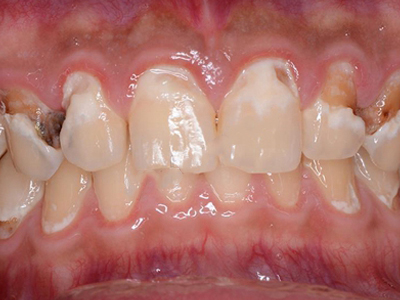

牙齿

缺损

酸蚀症牙齿缺损严重有黑斑图

酸蚀症严重时会使牙齿出现大面积缺损,有三颗下牙损毁严重,露出不整齐的牙骨质边缘,几乎仅余留牙根。缺损处有黑斑,局部呈黄褐色,需积极就医进行牙齿修复。